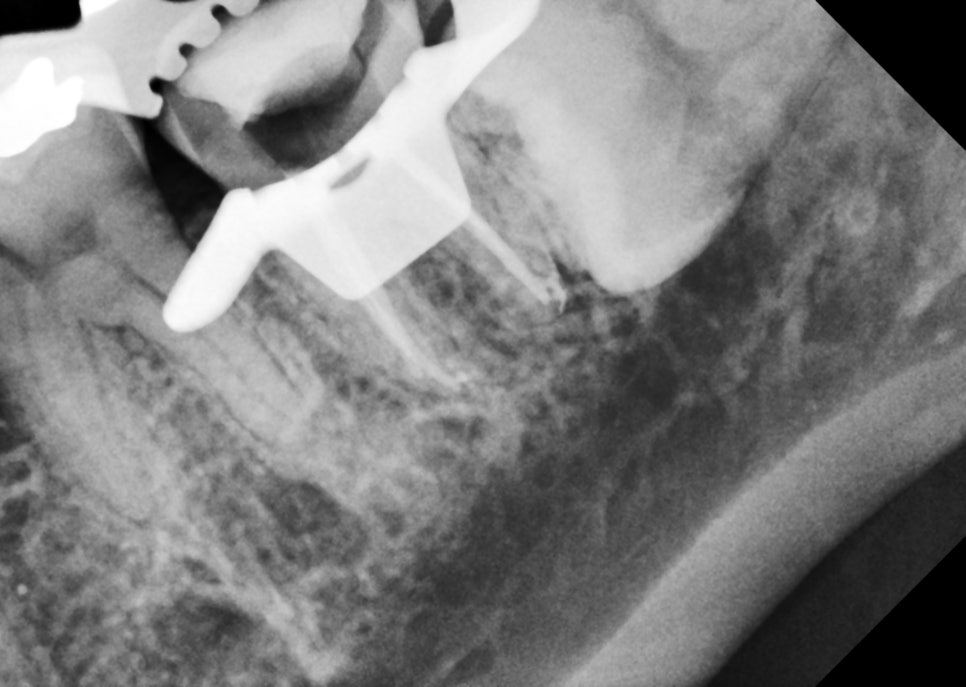

신경치료 하는 도중에도 아파하시고

신경관 바닥에도 크랙 라인으로 의심되는

선들이 관찰돼서 저도 걱정이 됐어요.

신경관에 소독약 담궈놓고 기다리기도 하고

초음파로 깨끗이 씻어도 주고

근관치료 완료